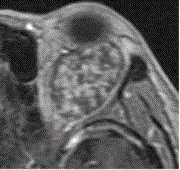

问题 患者女,30岁,左眼球突出,运动障碍7个月。MRI平扫示左肌锥内等T信号影(下图)。增强扫描示均匀增强,眼肌、眼环正常。 诊断应为

选项 A.甲状腺性突眼 B.眼眶疏松结缔组织炎 C.炎性假瘤 D.海绵状血管瘤 E.转移瘤 F.淋巴管瘤

答案 D